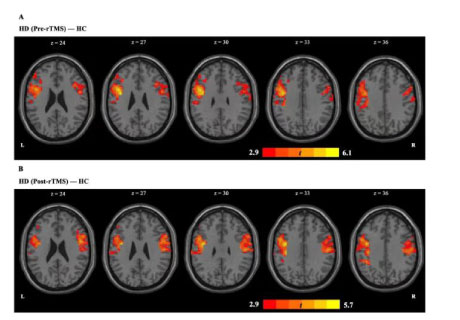

背景介紹海洛因成癮的定義為強(qiáng)迫性海洛因?qū)で蠛拖M(fèi)行為,盡管意識(shí)到嚴(yán)重的負(fù)面后果,可導(dǎo)致嚴(yán)重的社會(huì)和個(gè)人問(wèn)題,如個(gè)人發(fā)病率、經(jīng)濟(jì)損失、公共衛(wèi)生危機(jī)和過(guò)度誘導(dǎo)的死亡率(Kolodny等,2015)。針對(duì)左側(cè)背外側(cè)前額..